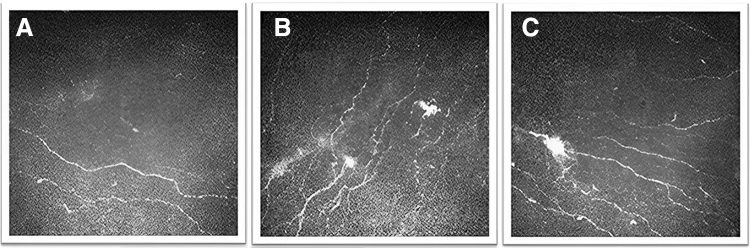

Blood-derived preparations, including autologous or allogenic serum, umbilical cord serum/plasma, and platelet-rich plasma eye drops, contain various growth factors, cytokines, and immunoglobulins that resemble natural tears. These components play important roles in corneal cell migration, proliferation, and wound healing. Blood-derived eye drops have demonstrated clinical effectiveness across a spectrum of ocular surface conditions, encompassing dry eye disease, Sjögren's syndrome, graft-versus-host disease, and neuropathic corneal pain (NCP). Currently, management of NCP remains challenging. The emergence of blood-derived eye drops represents a promising therapeutic approach. In this review, we discuss the benefits and limitations of different blood-derived eye drops, their mechanisms of action, and treatment efficacy in patients with NCP. Several studies have demonstrated the clinical efficacy of autologous serum eye drops in relieving pain and pain-like symptoms, such as allodynia and photoallodynia. Corneal nerve parameters were also significantly improved, as evidenced by increased nerve fiber density, length, nerve reflectivity, and tortuosity, as well as a decreased occurrence of beading and neuromas after the treatment. The extent of nerve regeneration correlated with improvement in patient-reported photoallodynia. Cord plasma eye drops also show potential for symptom alleviation and corneal nerve regeneration. Future directions for clinical practice and research involve standardizing preparation protocols, establishing treatment guidelines, elucidating underlying mechanisms, conducting long-term clinical trials, and implementing cost-effective measures such as scaling up manufacturing. With ongoing advancements, blood-derived eye drops hold promise as a valuable therapeutic option for patients suffering from NCP.

Abstract Image